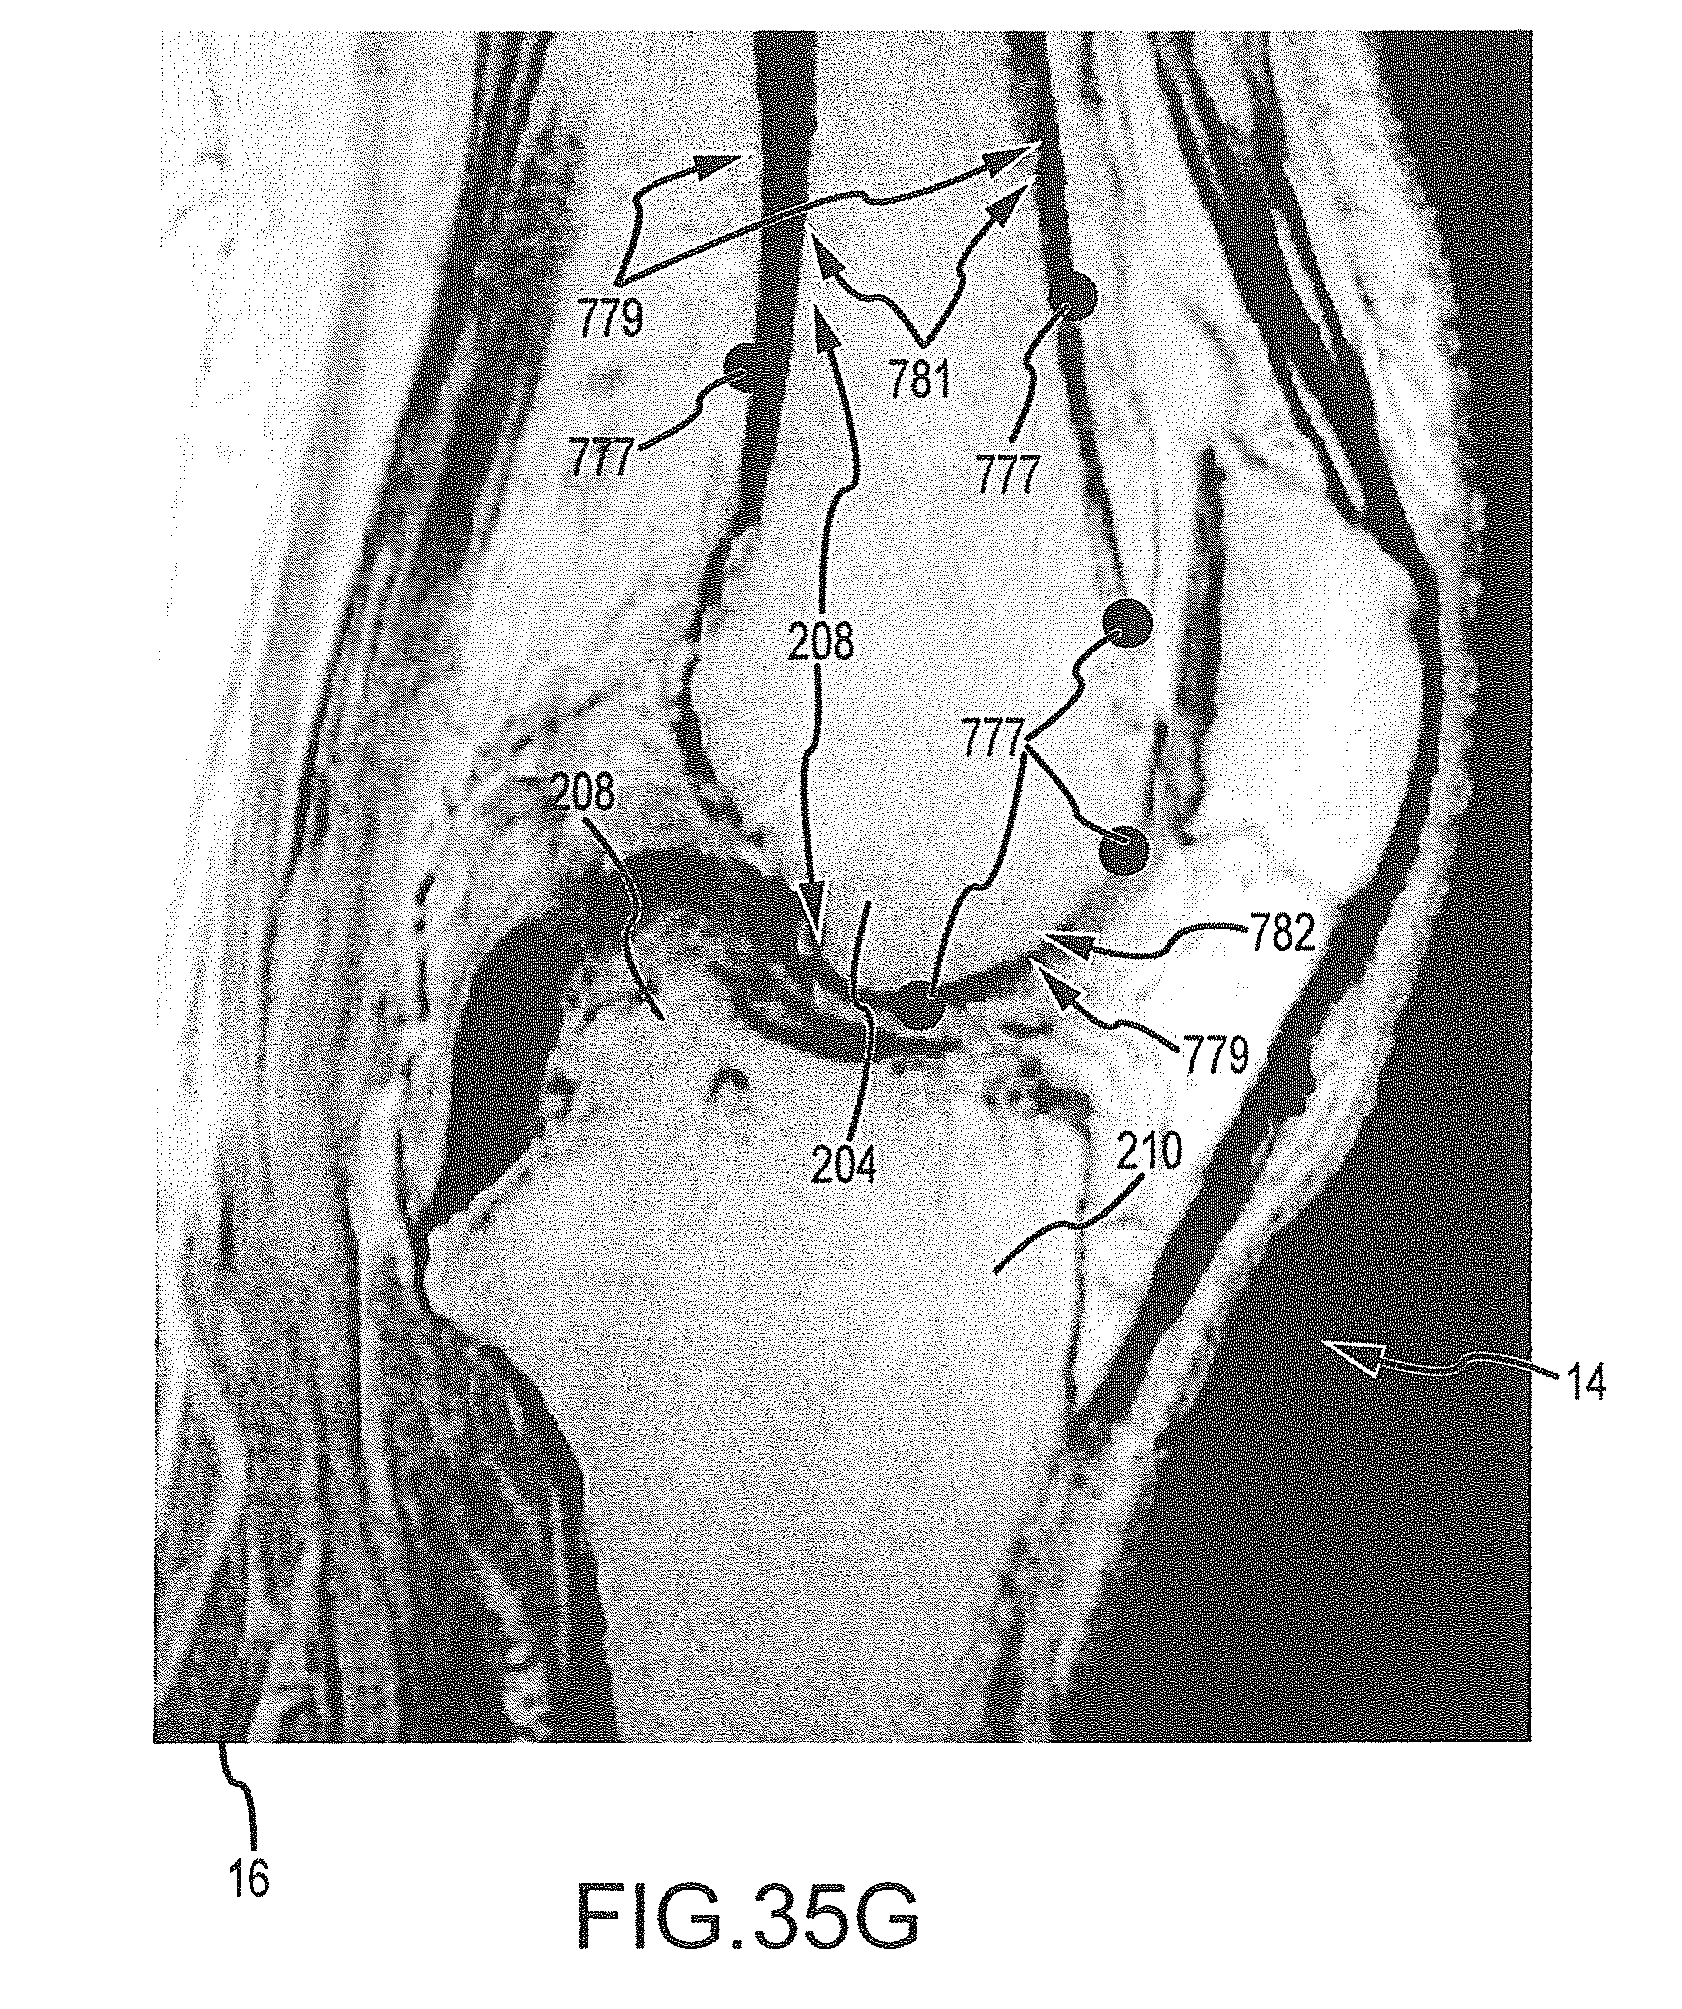

FIGS. 35A-35H are a series of sagittal image slices wherein landmarks have been placed according the process of FIG. 34.

FIG. 38B is an image slice with a contour line representing the approximate segmentation mesh surface found in operation 770c of FIG. 37, the vectors showing the gradient of the signed distance for the contour.